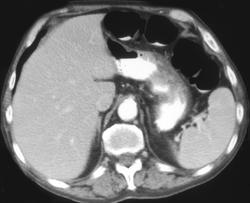

Diagnosis

Linitis Plastica